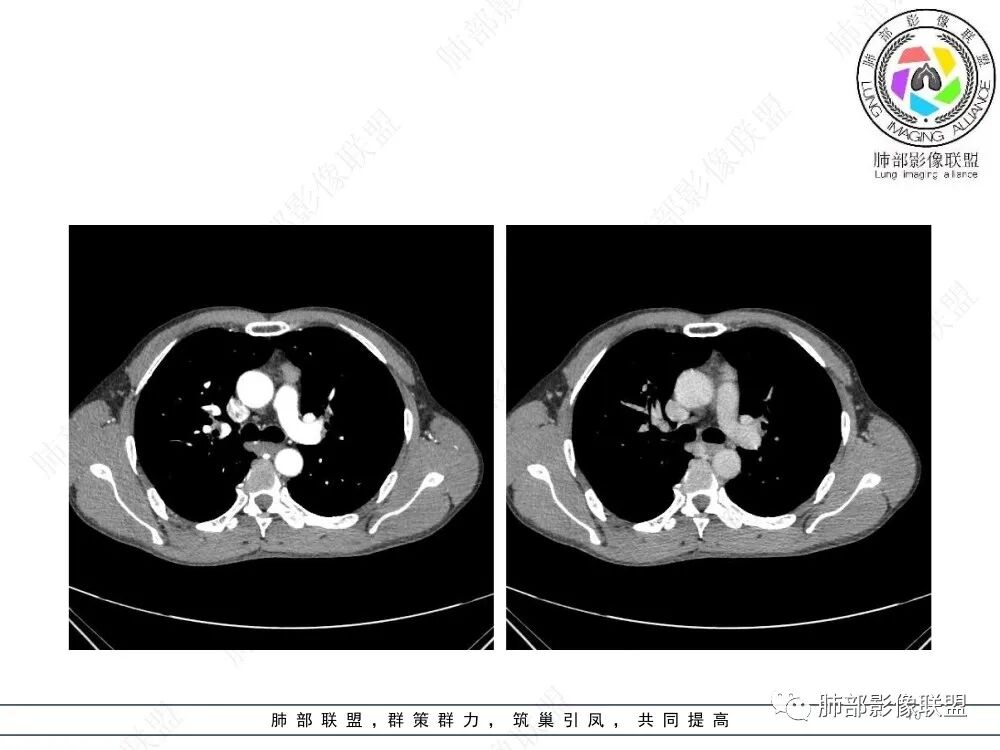

2、影像特点:前纵隔偏左侧软组织影,密度相对均匀,未见明显包膜钙化及实质内钙化,局部边缘浅分叶,周围脂肪间隙密度增高、浑浊,未见侵犯大血管、未见纵隔内淋巴结转移、未见侵犯心包内结构、未见胸膜转移结节、未见肿块沿着纵隔胸膜蔓延,未见胸腔积液。增强后动脉期不均匀强化,未见明显纤维分隔。

3、 病 例 小 结:40岁以上,前纵隔偏侧性生长的肿块,常规考虑胸腺瘤。难点就在于胸腺瘤的分型。但是对于前纵隔占位影像诊断的关键在于区分胸腺囊肿、胸腺瘤、胸腺癌及其他恶性肿瘤。至于胸腺瘤,主要在于判断有无侵袭性。

流心明智:男,47,咳嗽、咳痰1年余。胸部CT:前纵膈偏左类圆形肿块,瘤肺界面清晰光整,纵隔侧部分层面絮状影?平扫密度较均匀,增强后轻度强化,内可见宽带及线样低密度分隔。邻近左上肺受压凹陷。考虑胸腺肿瘤,AB型?胸腺Ca?鉴别淋巴瘤、N源性肿瘤、CD等。

南边:支持前纵隔、胸腺瘤首选,晨读其实定位上还是有点难度,定性常规还是考虑胸腺瘤,其他的几率比较低一些,需要鉴别的是胸膜SFT,神经源性,可惜的是没重建,一直在犹豫胸膜来源的可能性。